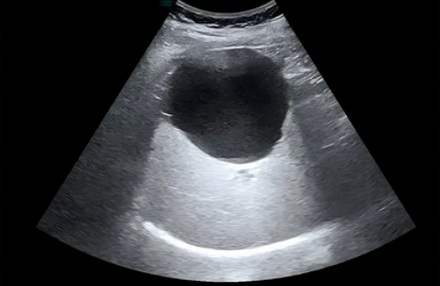

✔ B 型超声 (Brightness Mode)

最广为人知的「B 超 」,可以把回声信号转化为灰度图像。